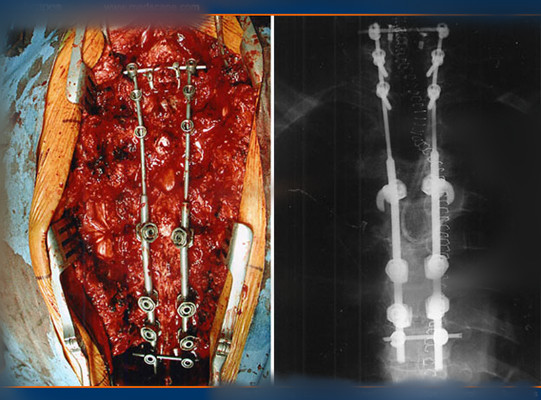

顱內血腫圖片

硬膜下血腫 (7)